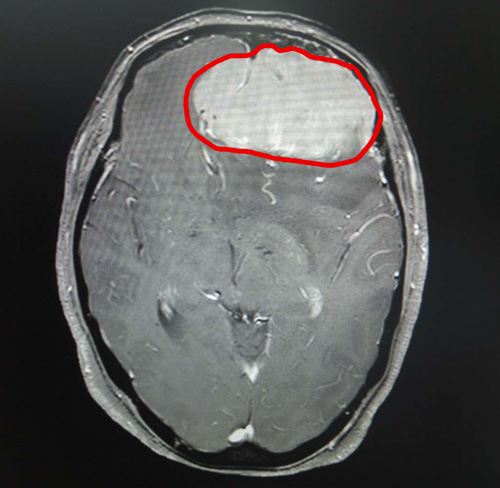

头颅MRI增强显示,丁阿姨的前颅窝有巨大的团块状异常信号。肿瘤大小约为6.9×5.6×5.4厘米,其大小与鸭蛋接近。

头颅MRI影像清晰显示了巨大的脑膜瘤

由于巨大肿瘤压迫患者不少重要的神经,肿瘤已将周围正常脑组织结构和主要脑供血动脉挤压得严重变形,手术难度很大。